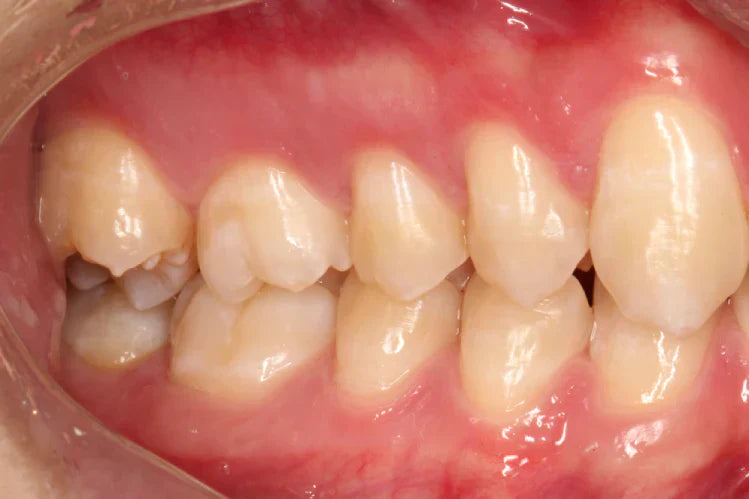

The posterior teeth, also known as teeth located at the back of the mouth are primarily responsible for chewing and grinding. Posterior teeth feature large sizes, are stronger than anterior teeth (incisors and canines), and are flat with cusps (bumps) designed for food breaking.

Adults possess eight premolars and twelve molars, including wisdom teeth at the end of the rows. The posterior teeth are crucial for chewing, maintaining the jaw's natural shape, and promoting dental health.

These two teeth, or bicuspids, are between the canines and molars. Because of their design, they are useful for tearing and crushing food. Premolars are transitional teeth that possess canine-molar characteristics.

Molar

The largest and strongest teeth are the molars, the broadest teeth in the mouth. They have broad surfaces with multiple cusps for grinding food. Adults usually have 12 molars, including wisdom teeth.